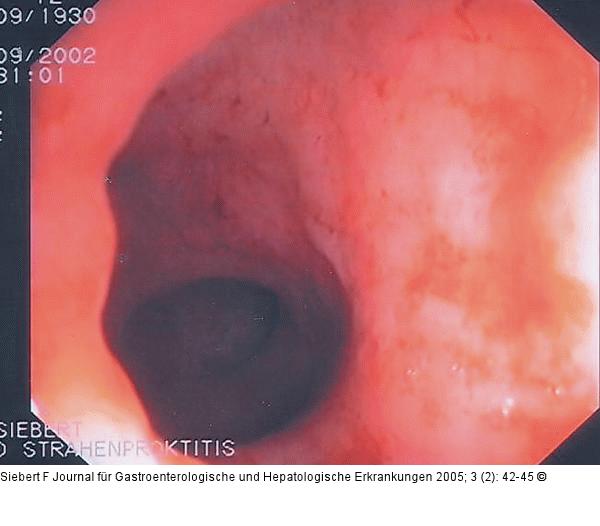

Abbildung 7a-c: Kolon-Ischämie - Differentialdiagnosen Differentialdiagnose Infektiöse Colitis - Strahlencolitis - Colitis ulcerosa (von oben nach unten) |

Abbildung 7b

Abbildung 7a-c: Kolon-Ischämie - Differentialdiagnosen

Differentialdiagnose Infektiöse Colitis - Strahlencolitis - Colitis ulcerosa (von oben nach unten) |